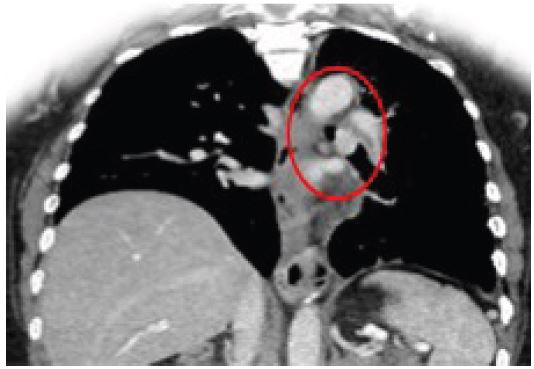

A 42-year-old male presented to our outpatient clinic with a 2-month history of persistent dry cough, mild exertional dyspnea, and occasional wheezing. He was a non-smoker with past history of Bronchial Asthma which was diagnosed 3 years back and patient was on Inhaled salbutamol on as needed basis. Clinical auscultation revealed a localized wheeze over the right lower lobe. Chest X-ray showed a suspicious opacity. CT chest revealed a well-defined lesion at the origin of the right lower lobe bronchus. Bronchoscopy visualized an endobronchial mass, and biopsy confirmed a typical carcinoid tumor.

Figure 2: CT axial image showing endobronchial lesion.

Figure 3: CT coronal image showing tumor obstructing the right lower lobe bronchus.